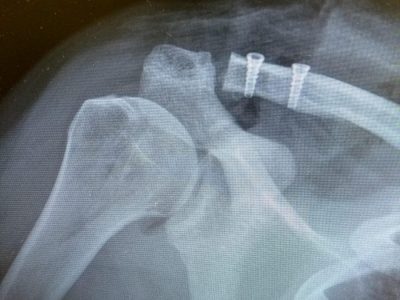

Παρακάτω παρατίθενται ακτινογραφίες καταγμάτων του άνω άκρου που αντιμετωπίζονται με εσωτερική οστεοσύνθεση ή επανορθωτική χειρουργική με αρθροπλαστική.